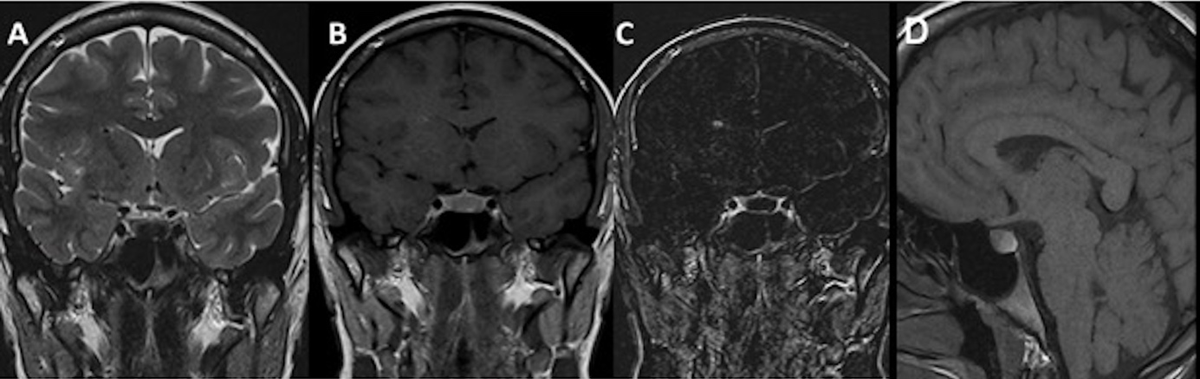

Figure 2

MRI after first surgery: Coronal T1WI (A), Coronal post-contrast T1WI (B) and coronal T2WI revealed signs of intracranial hypotension: right and left subdural collections and pachymeningeal thickening and enhancement.